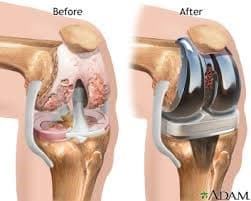

Өвдөгний үе бүтэн солих мэс засал (TKA) image1

Хагалгааны өмнө

Хагалгааны дараах